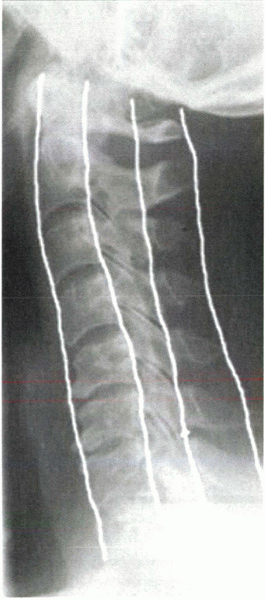

combined with postmyelography CT to assess the spinal structures

adequately (Fig. 2-2).

![]() |

|

Figure 2-2 Normal CT myelogram shows excellent spatial resolution and detail.